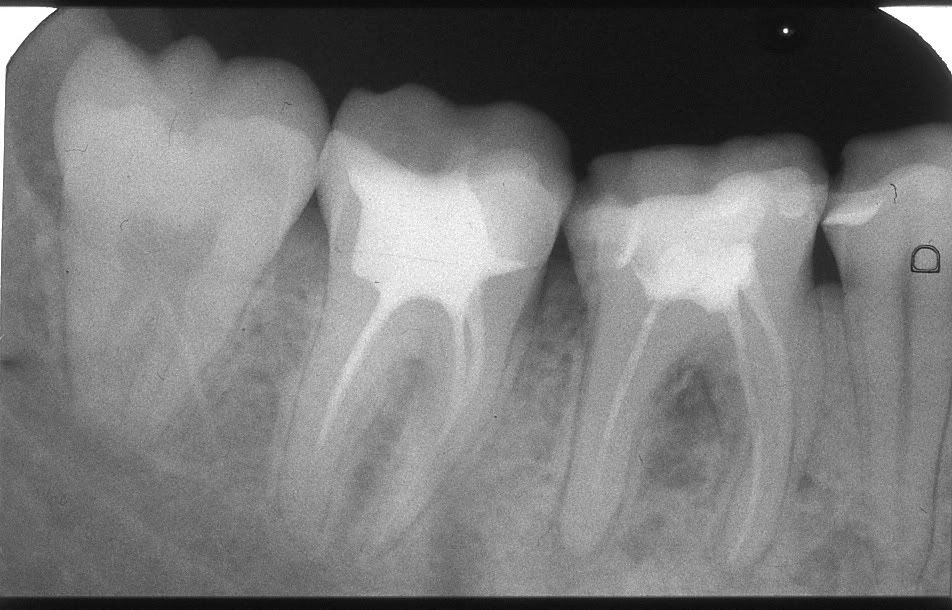

надо ли перелечивать каналы